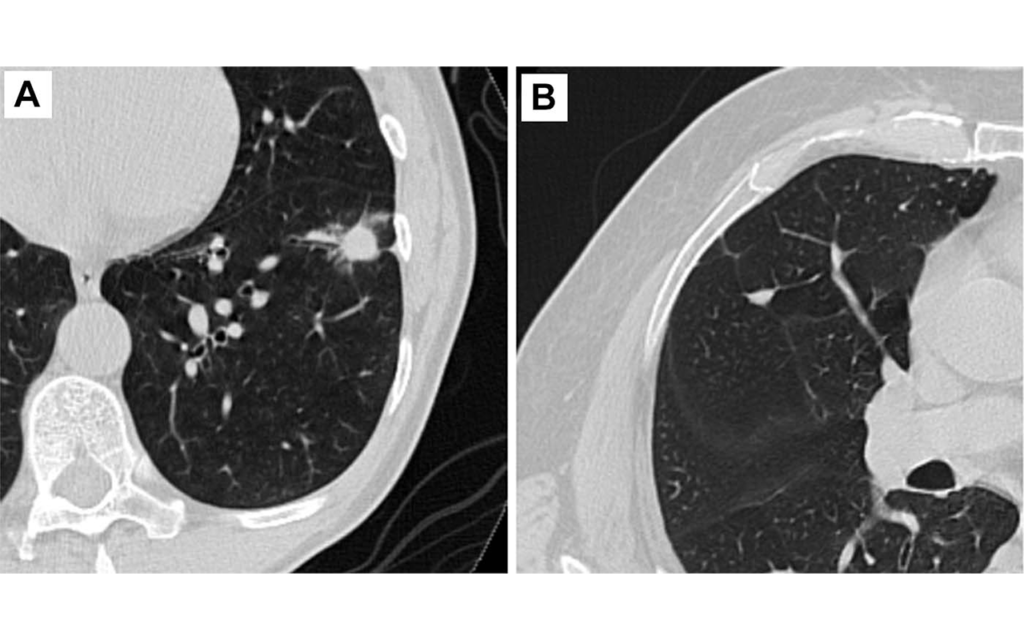

Pulmonary nodules appear as small spots on the lungs on chest imaging. They have become a much more common finding as CT has gained favor over X-rays for chest imaging.

Vachani and colleagues evaluated an AI-based computer-aided diagnosis tool developed by Optellum Ltd. of Oxford, England, to assist clinicians in assessing pulmonary nodules on chest CT. While CT scans show many aspects of the nodule, such as size and border characteristics, AI can delve even deeper.

A total of 300 chest CTs of indeterminant pulmonary nodules were used in the study. The researchers defined indeterminant nodules as those between 5 and 30 millimeters in diameter.